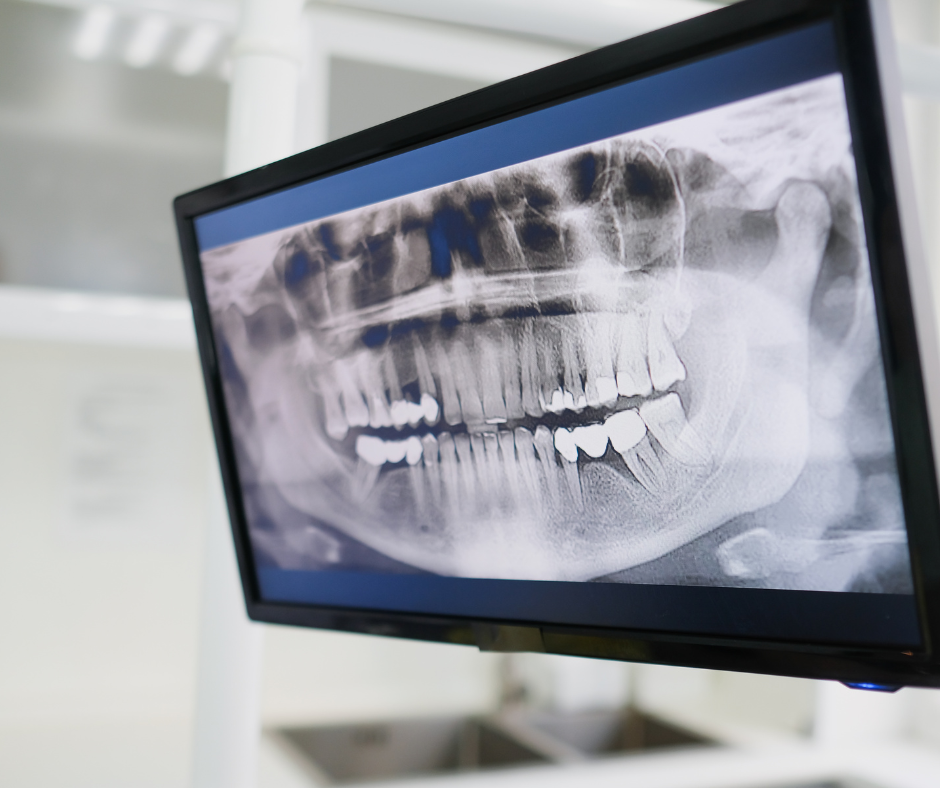

1. Точная диагностика

Осмотр, рентген или КТ позволяют определить:

• уровень костной ткани;

• стадию процесса;

• наличие воспаления.

Без этого лечение невозможно.